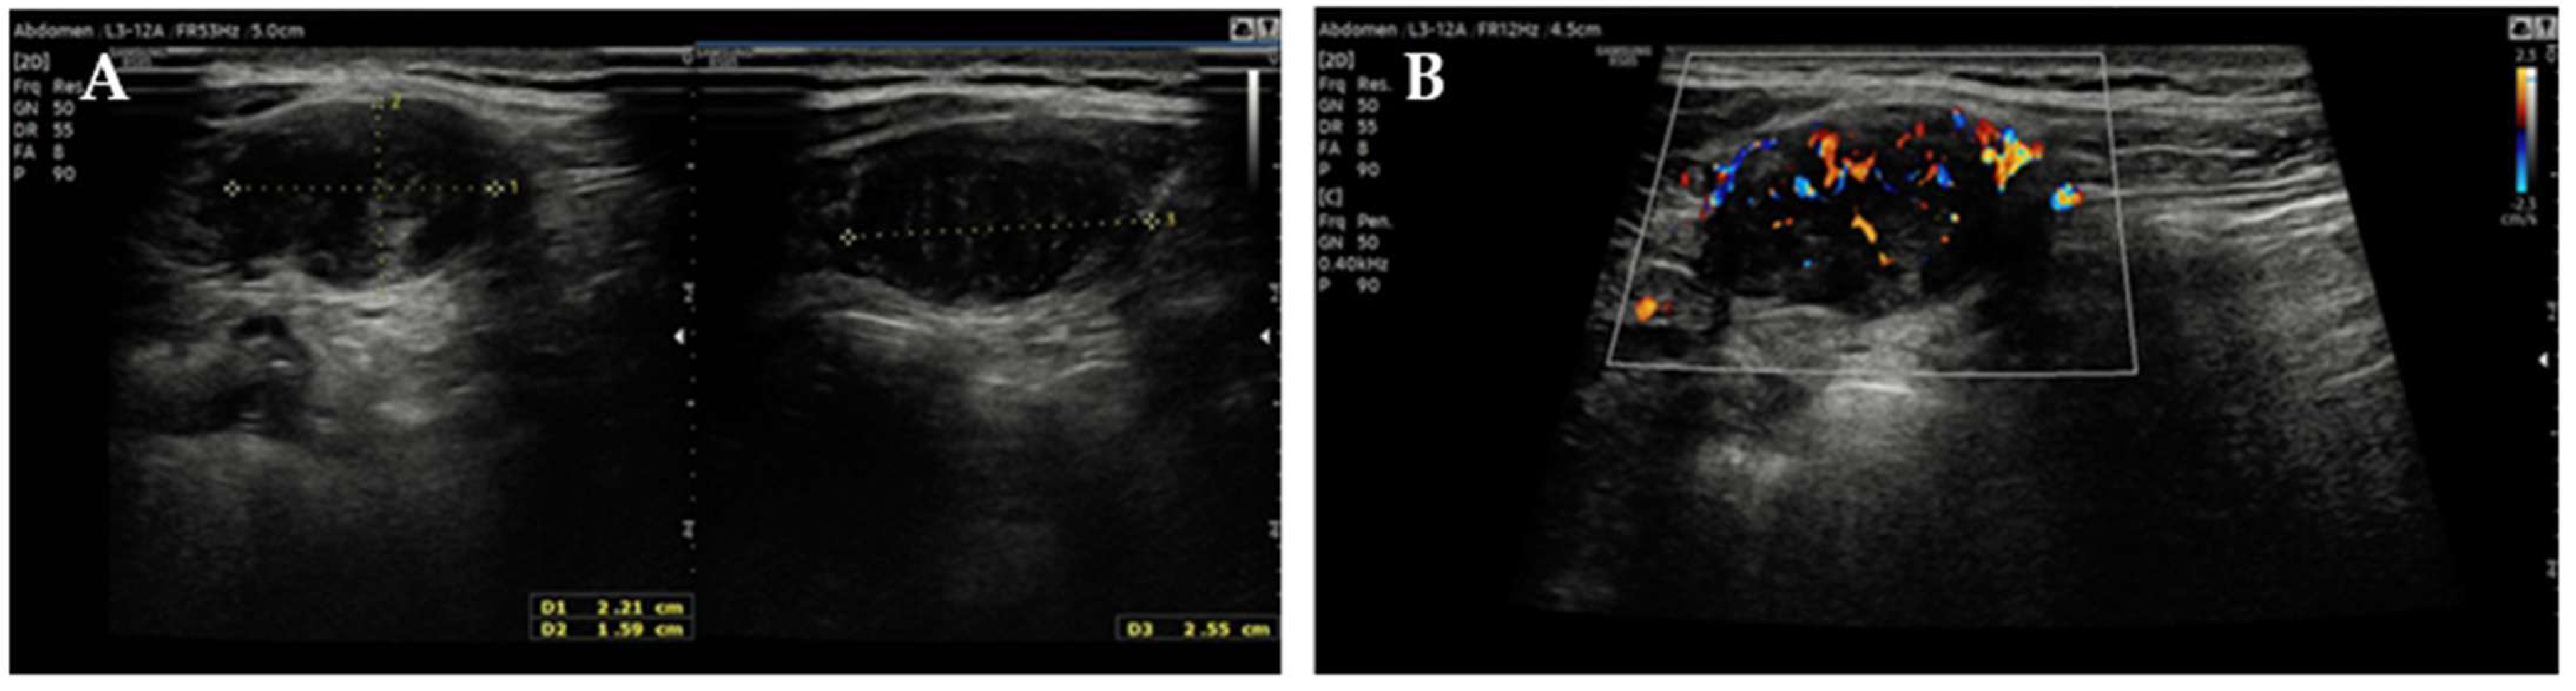

Follow-up MRI (May 2023) performed elsewhere revealed a solid, ovoid, hypointense nodule located between the right internal oblique and transversus abdominis muscles, described as consistent with fibrotic sequelae of endometriosis. Transabdominal US performed at our Clinic, confirmed a well-circumscribed, hypoechoic, moderately vascular lesion measuring 22 × 16 × 25 mm (Figure 1). Planned excision was postponed when the patient conceived again through IVF.

Figure 1.

Transabdominal US of the right abdominal wall: (A) measurements of the lesion and (B) its color-Doppler vascularization.